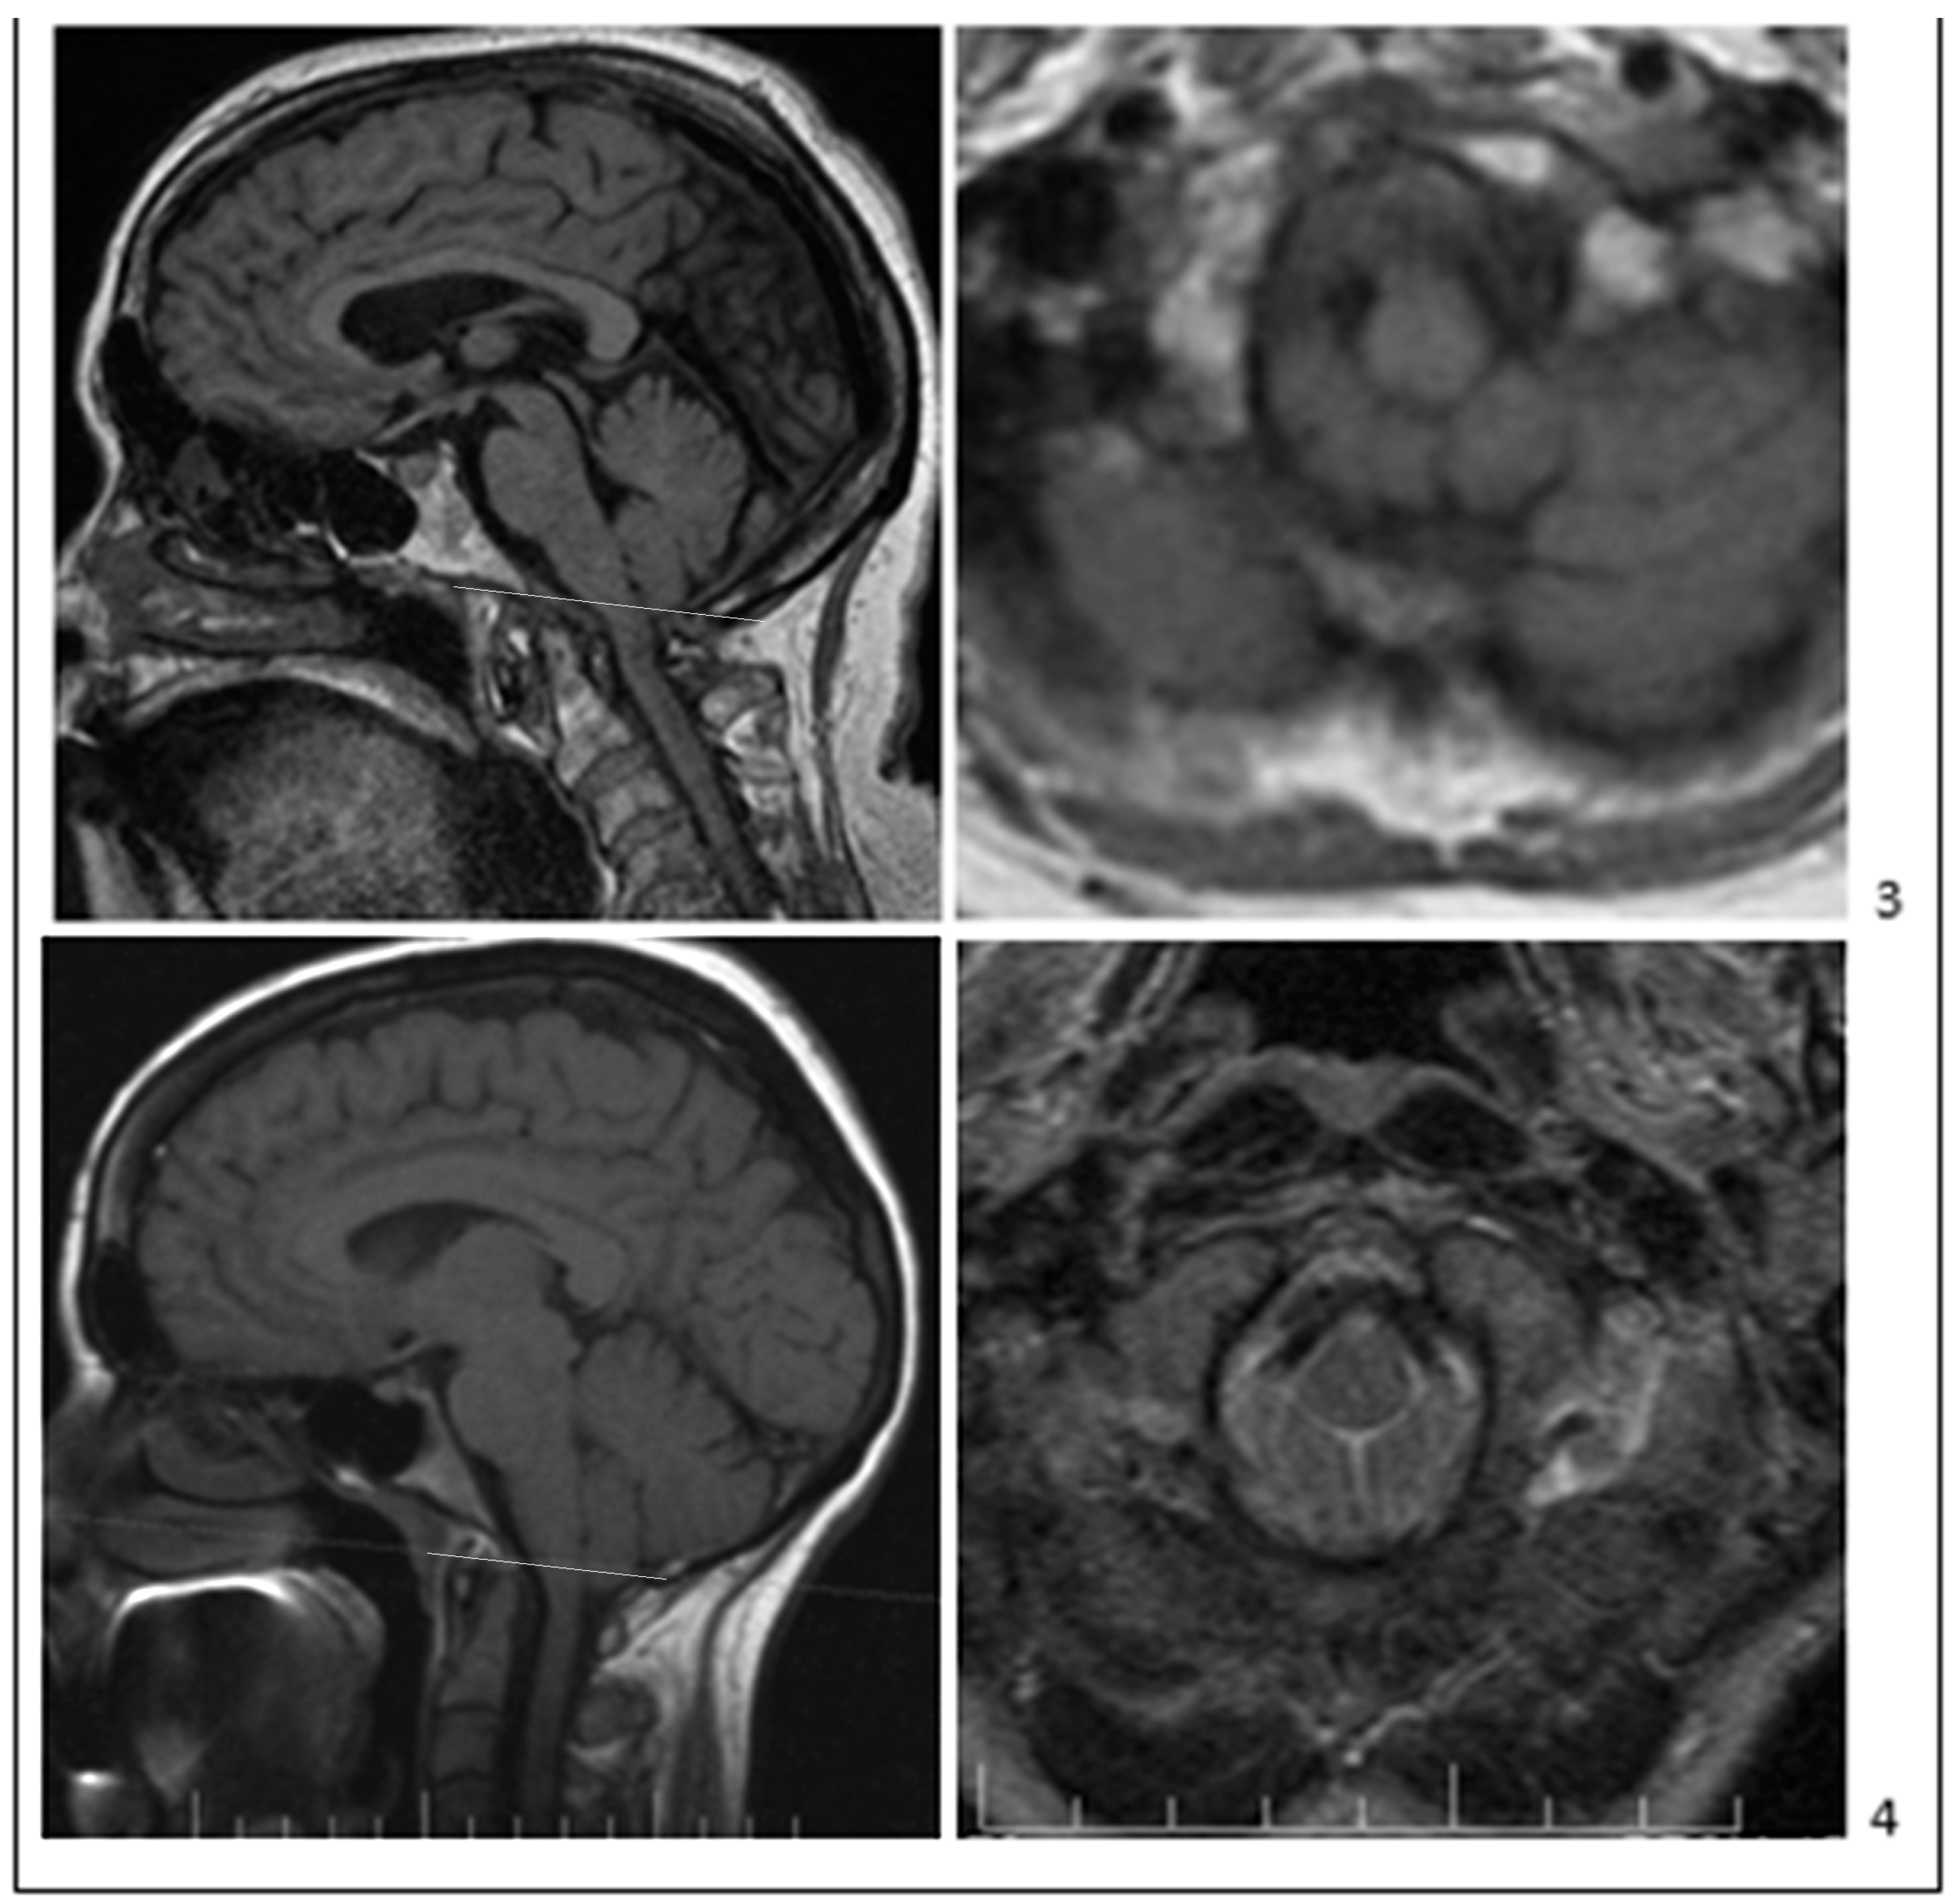

- Bogdanov, E.I.; Faizutdinova, A.T.; Heiss, J.D. Posterior cranial fossa and cervical spine morphometric abnormalities in symptomatic Chiari type 0 and Chiari type 1 malformation patients with and without syringomyelia. Acta Neurochir. 2021, 163, 3051–3064. [Google Scholar] [CrossRef]